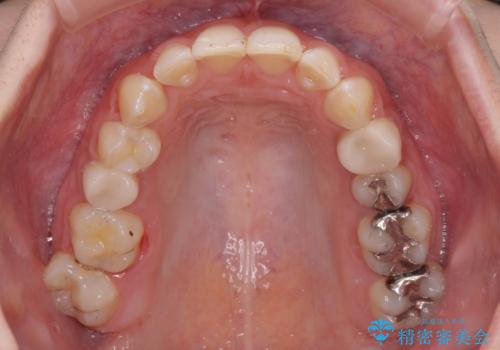

- 前歯の歯列不正を気にして来院された患者様です。

インビザラインでの矯正治療を希望されていましたが、奥歯の咬み合わせがインビザライン単独では改善困難と判断されたので、補助装置を併用することとしました。

まずは裏側の装置やワイヤー矯正を用いて歯列幅の狭い上顎を側方に拡大しつつ全体を後方に移動させ、その後インビザラインにて歯列を整えることとしました。